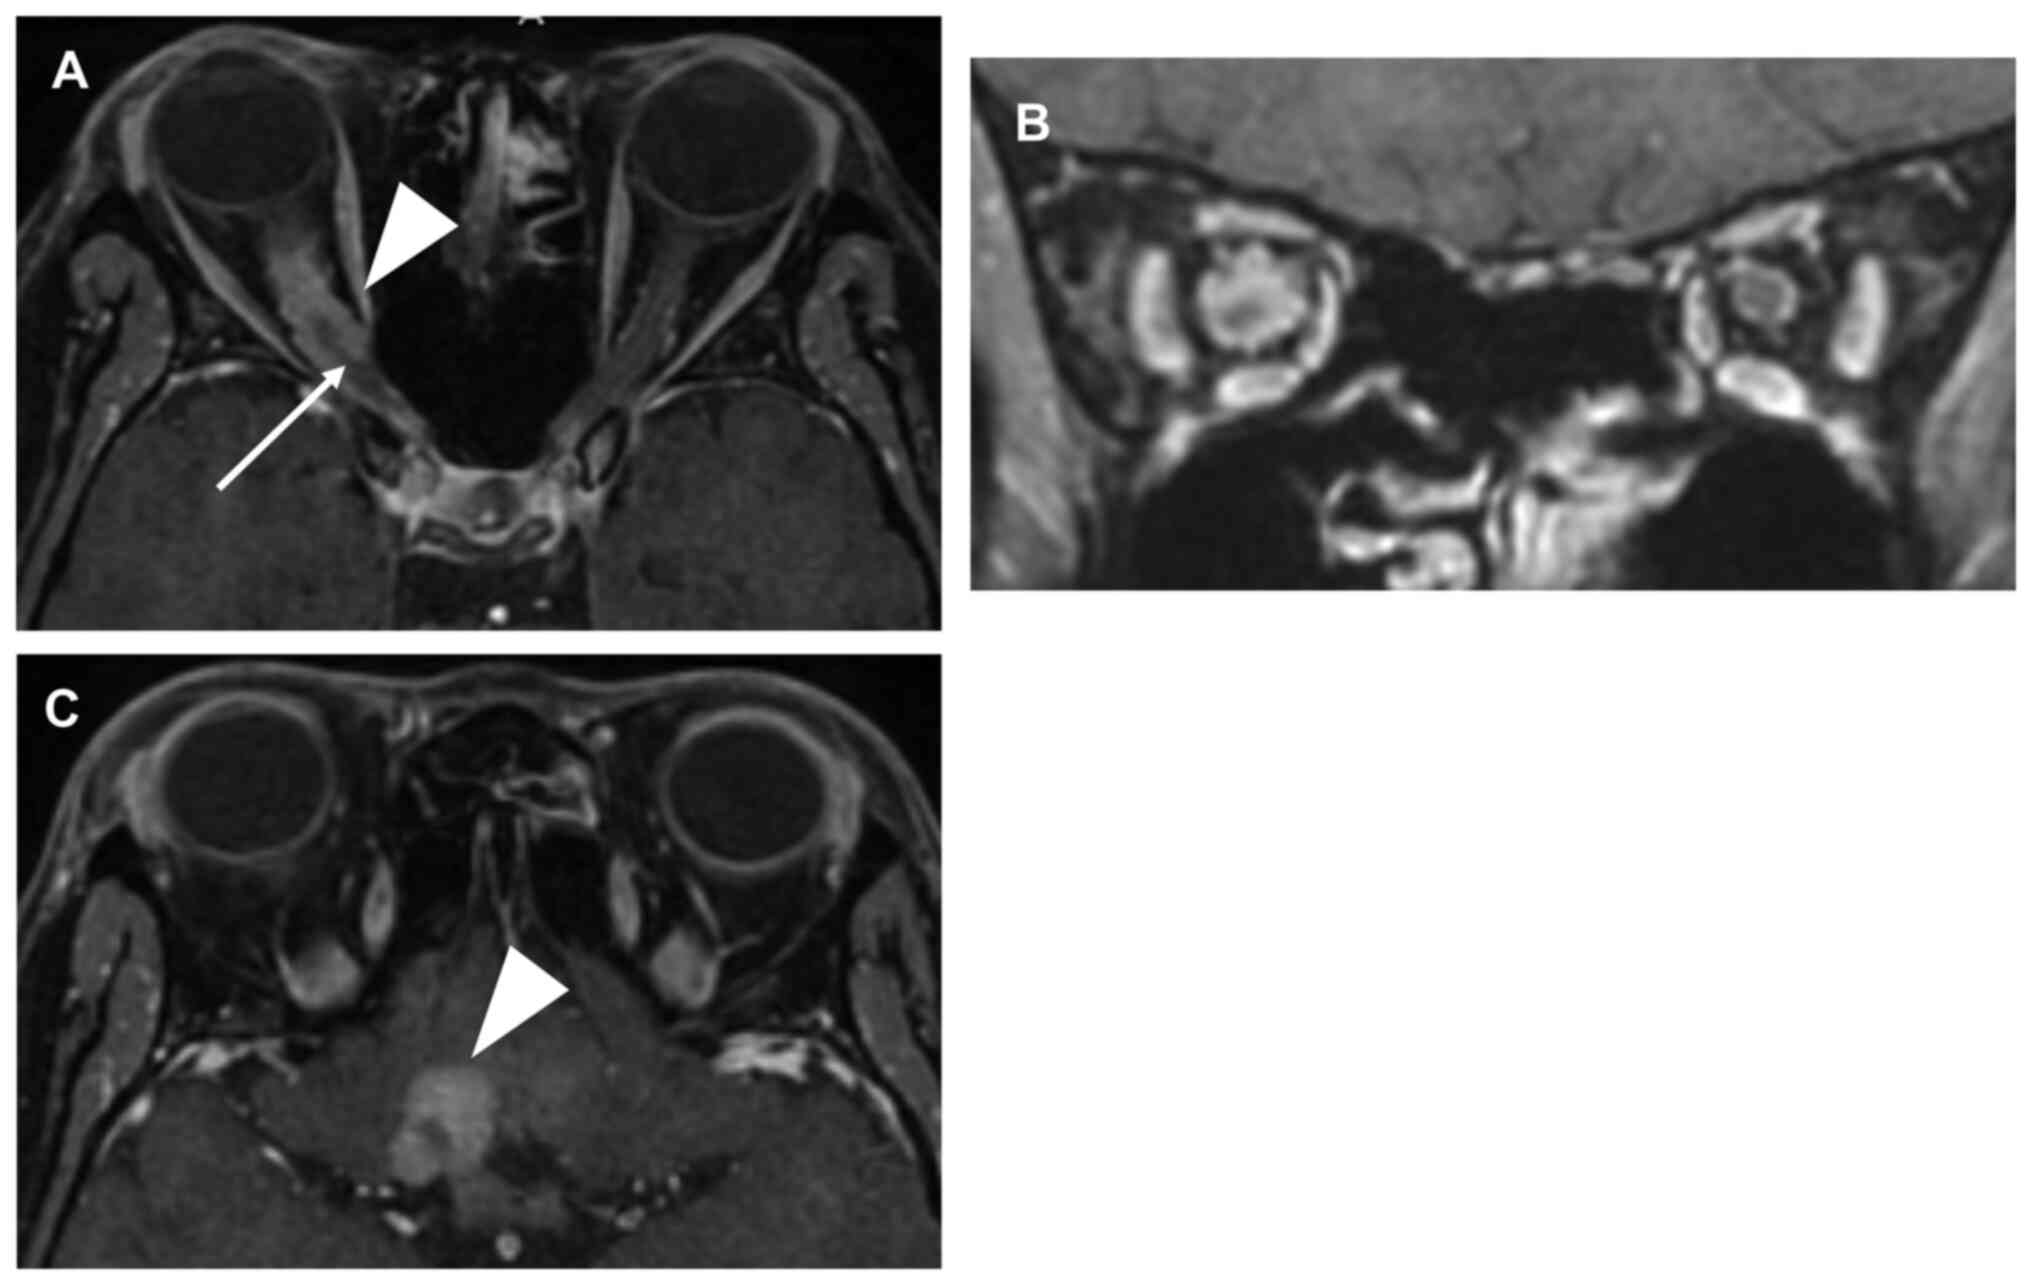

A 41-year-old woman felt visual impairment in the right eye, late in her first pregnancy. After the delivery, she received an ophthalmic examination and both visual acuity and field were normal. After 2 years, during late pregnancy with her second child, she became aware of slowly progressive visual deterioration in the right eye again. Two months after the second delivery, fundus examination showed swelling of the right optic disc. She was diagnosed with optic neuritis and received steroid pulse therapy. After 1 year, swelling of the right optic disc and right visual impairment had progressed. Her right eye's visual field was impaired, and she had developed lateral lower quadrantanopia. Furthermore, her right visual acuity worsened from 20/20 to 20/200 corrected visual acuity over the course of 1 year. She was admitted at our hospital and underwent magnetic resonance imaging (MRI). MRI revealed an intraconal tumor encasing the right optic nerve (Fig. 1A and B). The tumor extended through the optic canal to the right carotid artery and close to the optic chiasm (Figs. 1C and 2A). Surgical resection of the intracranial extension of the tumor was performed to prevent tumor invasion of the left optic nerve and the optic chiasm (Fig. 2B). After resection, the bilateral optic nerves were confirmed to be intact. The dura of the frontal base was coagulated and incised using a low-power bipolar system and micro dissection needle to prevent tumor invasion of the left optic nerve along the dura matter. The intraconal portion of the tumor encasing the right optic nerve was not resected to prevent compromising visual function. After intracranial tumor resection, her visual acuity maintained the presurgical value of 20/200 corrected visual acuity. The pathological findings suggested angiomatous meningioma, WHO Grade 1 with positive immunostaining for PR and negative for estrogen receptor (ER). Seven months after operation, her visual function did not deteriorate. MRI revealed no tumor size change during the 7-month observative follow-up period. There is a possibility that tumor size may be stable due to reduced influence of progesterone after delivery. We have planned adding high-precision radiotherapy when the tumor grows to achieve our goals of tumor control and preservation of visual function.

Figure 1

(A) Contrast-enhanced MRI showing thin right optic nerve (arrow) and ONSM encasing the right optic nerve (arrowhead). (B) MRI showing homogeneous enhancement with a ‘tram-track sign’ around the non-enhancing right optic nerve. (C) ONSM extends to the right carotid artery, close to the optic chiasm (arrowhead indicates meningioma). MRI, magnetic resonance imaging; ONSM, optic nerve sheath meningioma.